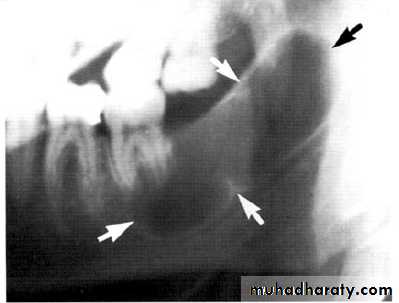

Multilocular appearance, expansion (arrowed) and considerable displacement of the adjacent teeth.

Buccal and lingual expansion (arrowed) and the undulating cortical border.

• Aneurysmal Bone Cyst

•Large multilocular aneurysmal bone cyst

in the ramus with marked expansion and

the displacement of/8.